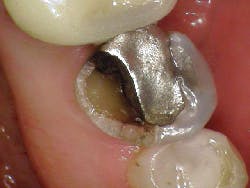

Diagnosis: Necrotic No. 3 with likely association of extended fracture line into the pulpal space. Recommendations were given to the patient, who opted for extraction and eventual implant placement. Upon removal of the tooth, the following was noted (figure 10):

- Lingual fracture line extending approximately 5 mm below the CEJ

- Existing restoration was removed and the crack line was observed to run across the pulpal floor in a mesiodistal fashion

- Wedging was done, and there was a noted flexuration in the cusps